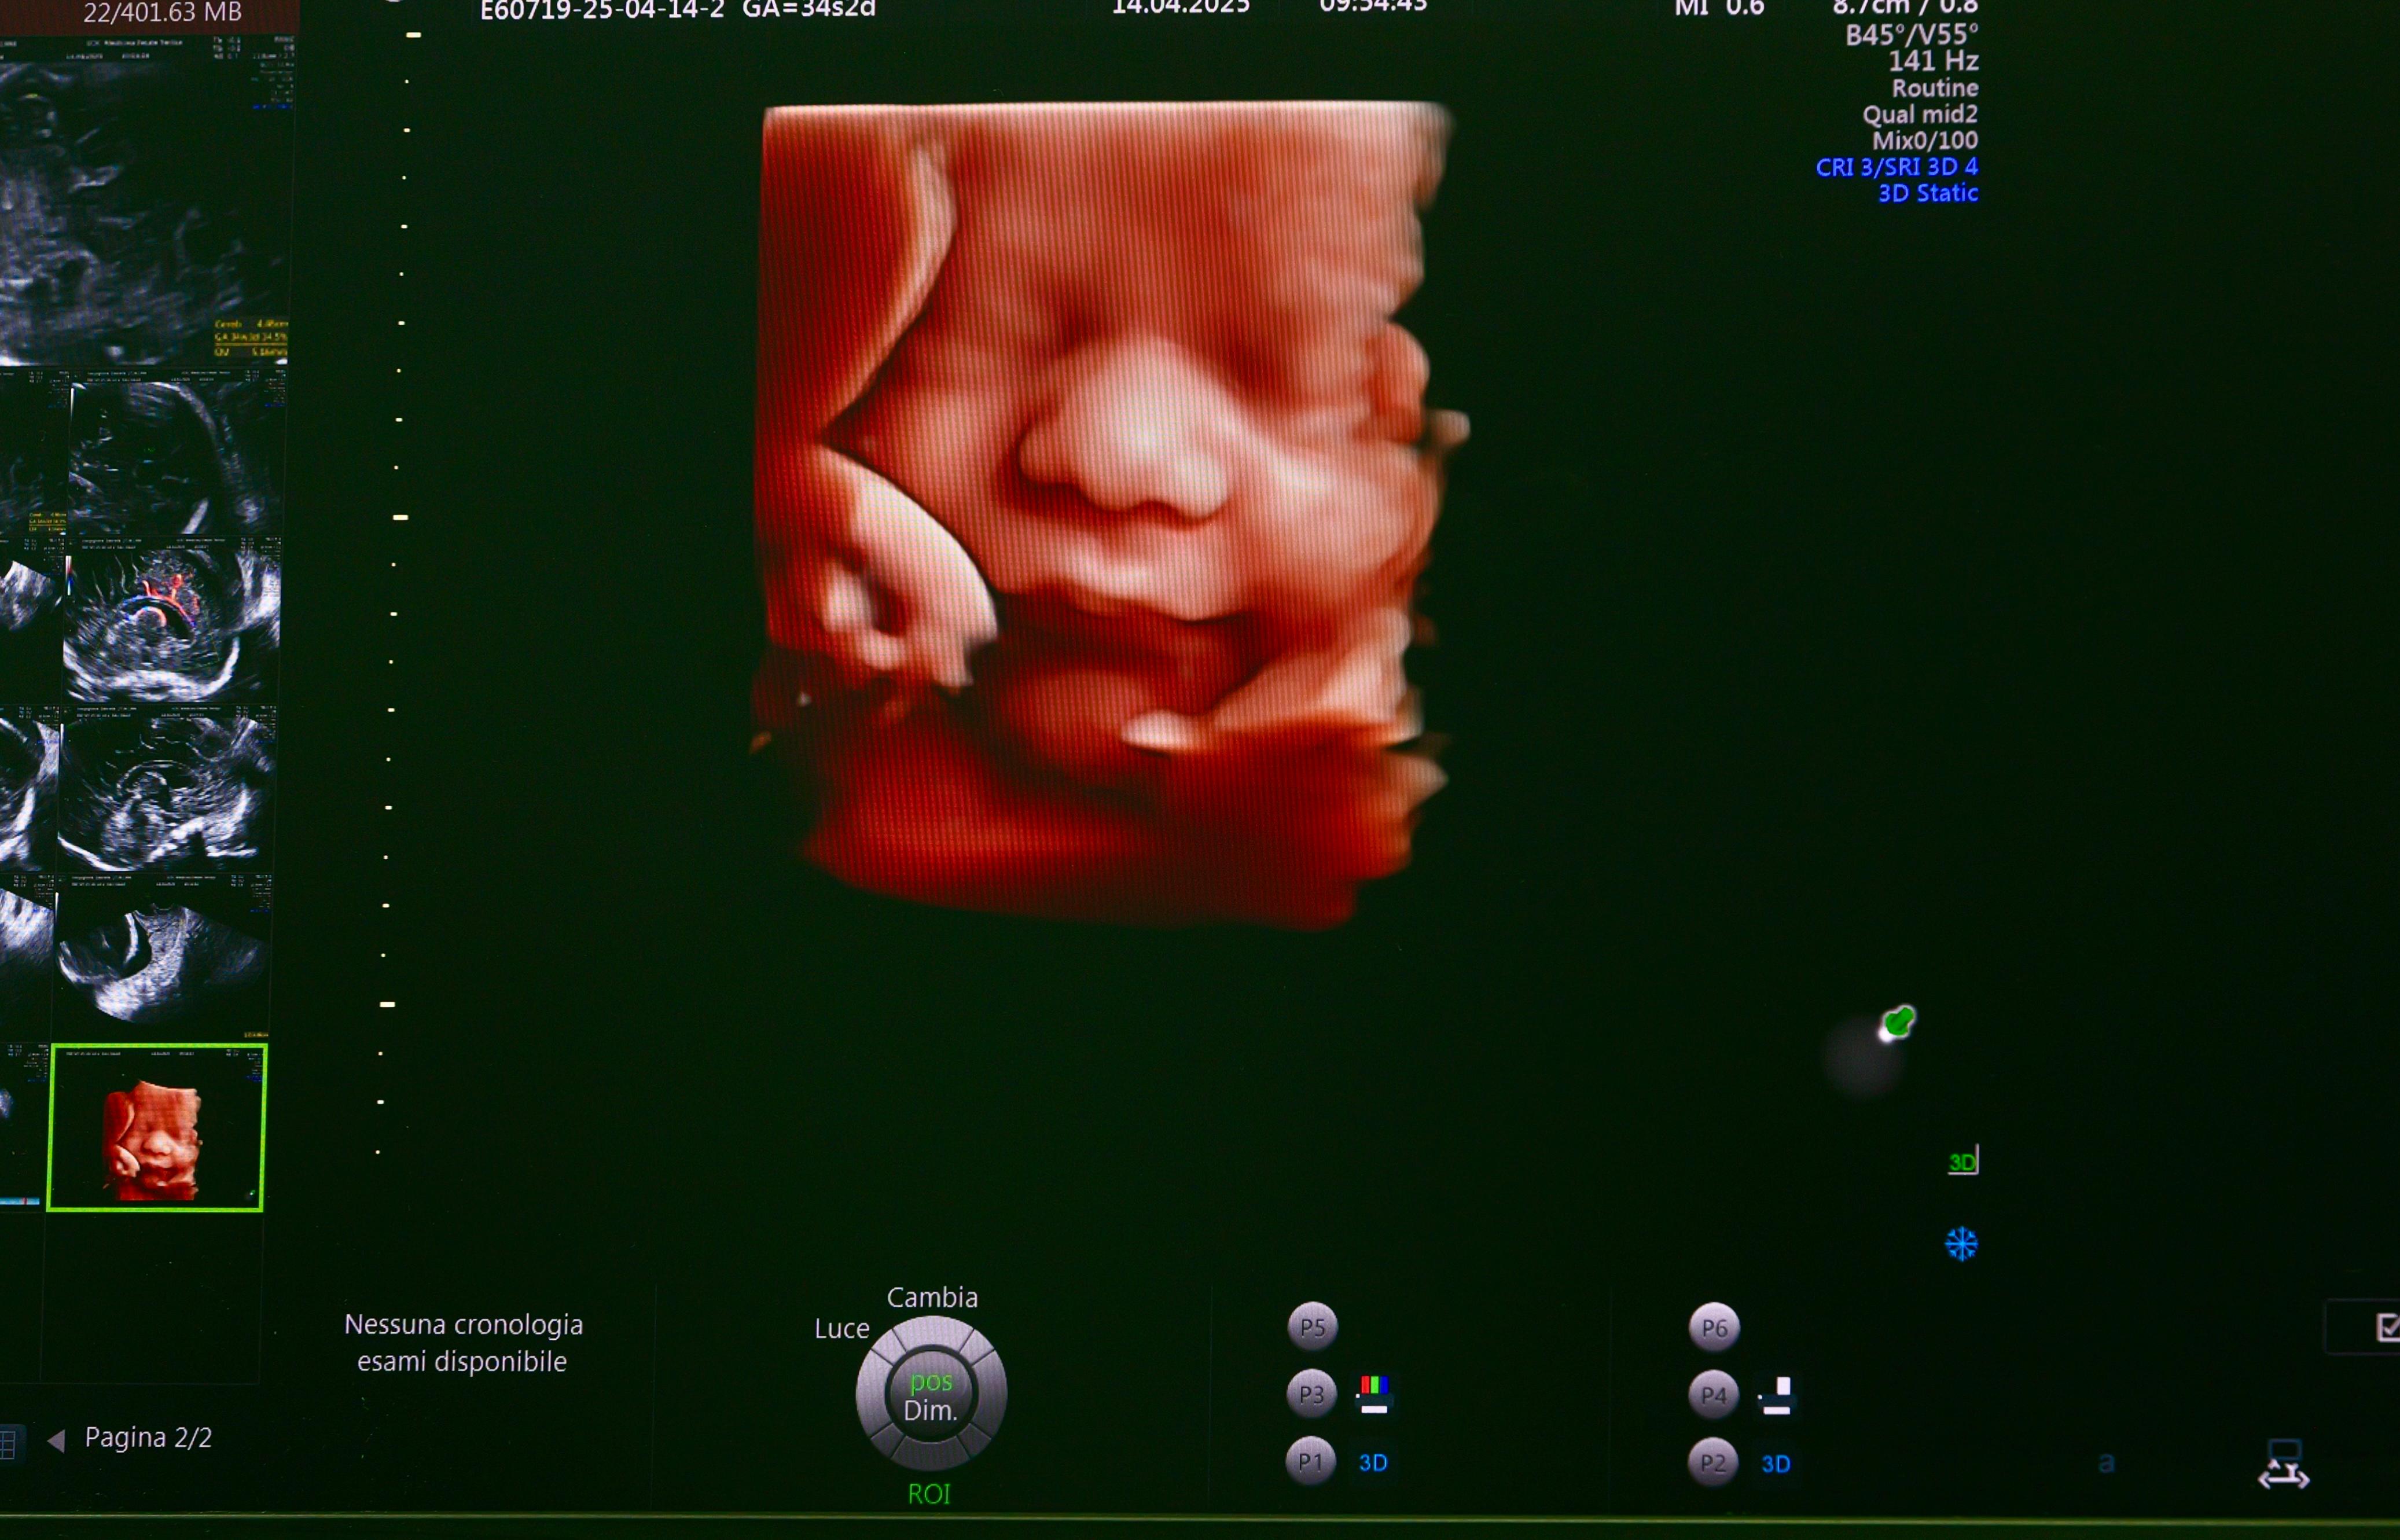

La Medicina fetale sul territorio

La nuova collocazione del Servizio di Medicina fetale è il risultato del potenziamento dell'offerta sanitaria all'interno del Presidio di Terlizzi, dove sono stati attuati una serie di interventi di ottimizzazione e riallocazione di altre attività con un investimento di fondi di circa 70.000 euro. Infatti, i locali dell'ex terapia intensiva al secondo piano dell'edificio sono stati rifunzionalizzati per ospitare sala d'attesa, accettazione, stanze per équipe medica ed ostetrica, due stanze per l'ecografia.

Una scelta lungimirante del dr. Paolo Volpe, direttore del Dipartimento Gestione Avanzata Rischio Riproduttivo e Gravidanze a Rischio, che ha voluto potenziare sul territorio le prestazioni specialistiche ambulatoriali già erogate all’Ospedale “Di Venere” e riguardanti le patologie del feto, la gravidanza gemellare monocoriale e in generale la gravidanza a rischio, attività per le quali tra il 2023 e 2024 sono state erogate oltre 17mila prestazioni (visite e diagnostica).